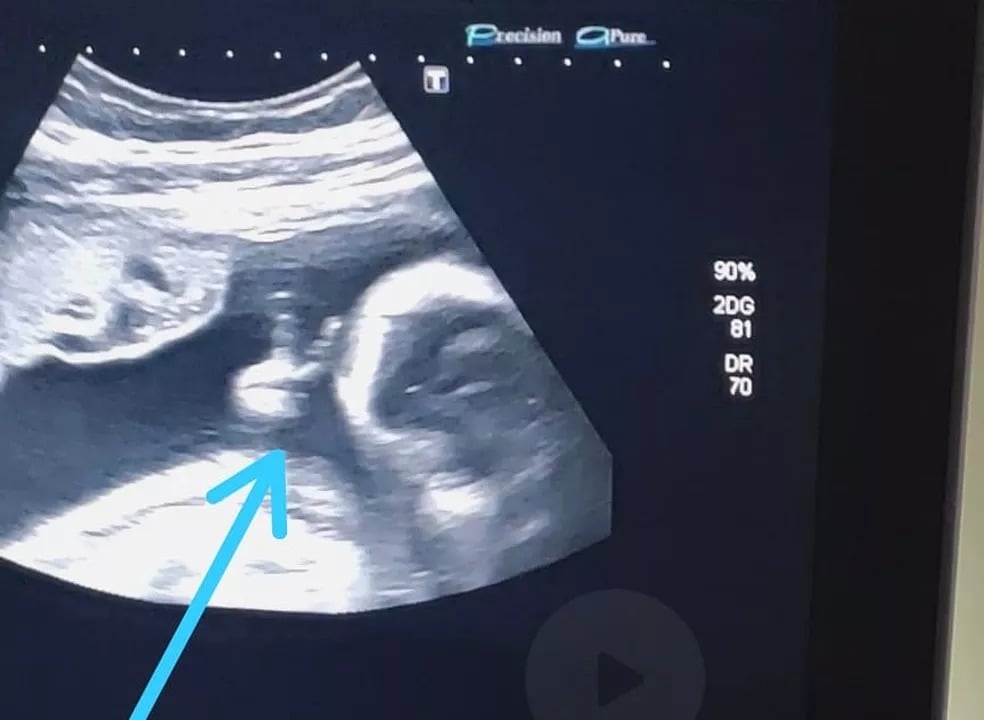

Ele conta que, ver o bebê e ouvir seu coração já é muito emocionante, mas desta vez puderam ver o pequeno Davi fazendo o sinal de “V” com a mão. “Até a médica falou: ‘olha, ele fez o sinalzinho de vitória com a mão’. Eu fiquei sem acreditar”, afirma Felipe.

Vendo a situação como um sinal divino, Felipe acredita que conseguirá superar o tratamento e vencer o câncer.